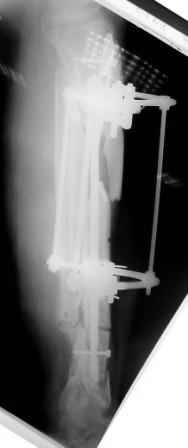

3) Третьим этапом наложили модуль на промежуточный фрагмент.(рис 3) И начали его транспорт на стержне в проксимальном направлении. (рис 3 а)

Надеемся что «вырастет» регенерат в дистальном отделе, а в проксимальном отделе фрагмент «упрется» и прирастет.